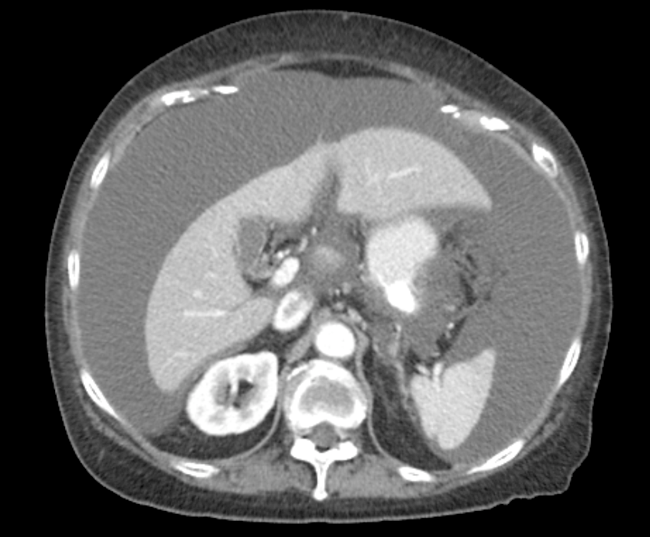

Ascites

Note the renal mass. Since it is not cystic in appearance it is malignancy until proven otherwise.